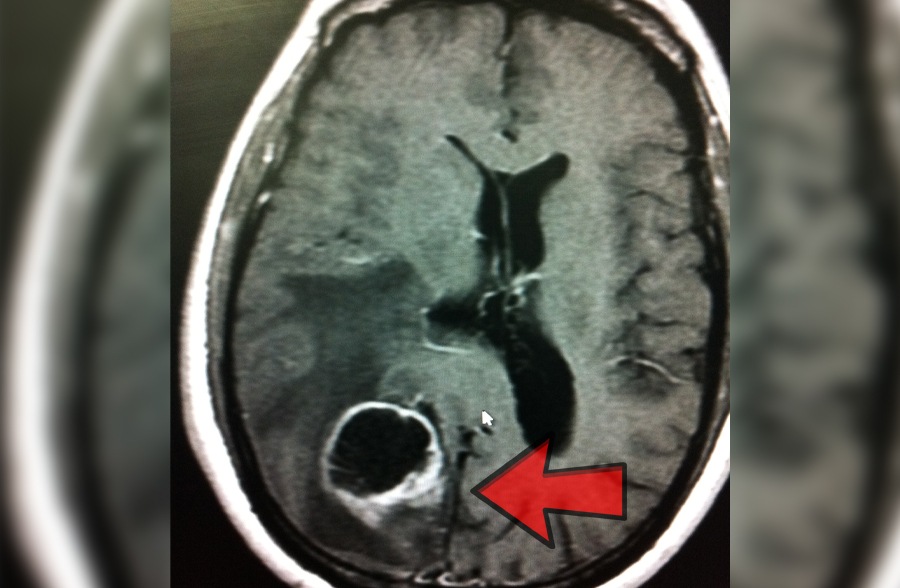

Tumores cerebrales

Los tumores se manifiestan por dolor de cabeza que no responde al manejo habitual.

También puede haber convulsiones, alteraciones de la fuerza de un lado del cuerpo o

afectación de la movilidad ocular o de la cara, vértigo, nauseas, vómitos, falta de coordinación, transtornos hormonales o visuales etc.

¡Es muy importante su detección temprana!